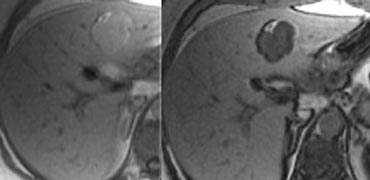

T2WI, T1WI without Gadolineum and a delayed phase after Gadolineum. T2WI, T1WI without Gadolineum and a delayed phase after Gadolineum.

If you look at the images on the left and just would consider the T2W-images, what could be the cause of the central area of high signal?

The most common cause would be central necrosis in a tumor.

However if you look at the delayed phase, you will notice that this area enhances.

So this is fibrotic tissue and the diagnosis is FNH.

Fibrolamellar carcinoma (FLC) has a dark scar on T2WI and FNH has a brigth scar on T2WI in 80% of the cases.

This means that at times the differential between FNH and FLC will not be possible.